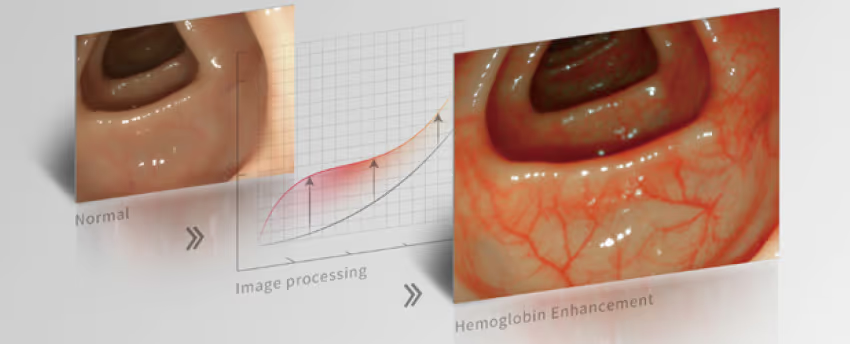

Fonksiyonu, kanı görüntüler ve endoskopi sırasında etkilenen dokulardaki olası kan akış yönünü vurgular.

Güçlü algoritmalar, klinik gözlem ve tanıyı kolaylaştırmak için üç modda görüntü ayrıntılarını geliştirir.